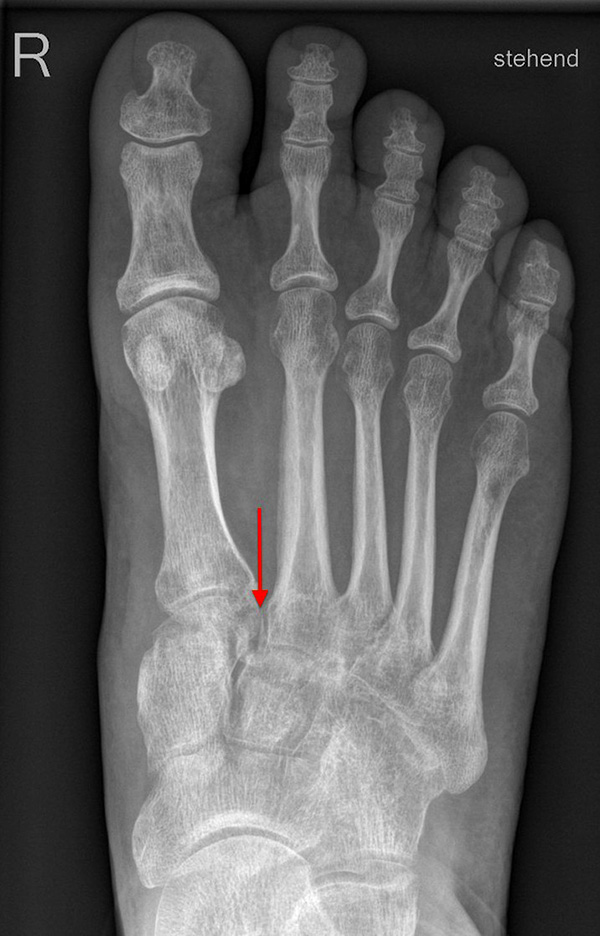

Auf den dp-Aufnahmen sollte der mediale Rand der Metatarsale-2-Basis mit dem medialen Rand des Os cuneiforme intermedium eine homogene Linie ohne Stufenbildung bilden (Abb. 7+8). Außerdem ist auf den Abstand zwischen der Metatarsale-1- und -2-Basis zu achten. Dieser sollte nicht größer als 2 mm bzw. im Vergleich zur Gegenseite nicht mehr als 1 mm erweitert sein. In bis zu 90% der Fälle zeigt sich ein sogenanntes „Fleck sign“ (Abb. 9), ein knöchernes Fragment zwischen der Metararsale-1- und -2-Basis im Sinne eines knöchernen Ausrisses des Lisfranc-Ligaments an der Metatarsale-2-Basis 211936410. Oft liegen zusätzliche Frakturen der Metatarsalebasen oder der Tarsale vor, die ebenfalls identifiziert werden sollten. Bei jeder Mittelfußbasisfraktur sollte umgekehrt an eine Lisfranc-Verletzung gedacht werden.

Zum Lesen der Bildbeschreibung und zur Vollansicht bitte die Bilder anklicken.